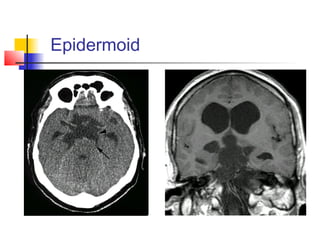

5. EPIDERMOID AND DERMOID

TUMORS

 Usually associated with hydrocephalus

because of CSF obstruction.Both do not

invade, they rather push.

 CT: both are hypodense and do not

enhance; dermoids have inclusions of

calcium and fat. MRI: epidermoids are of

CSF density; dermoids are hypointense in

T1 and hyperintense in T2.

 Surgical removal is the best treatment.

Epidermoid